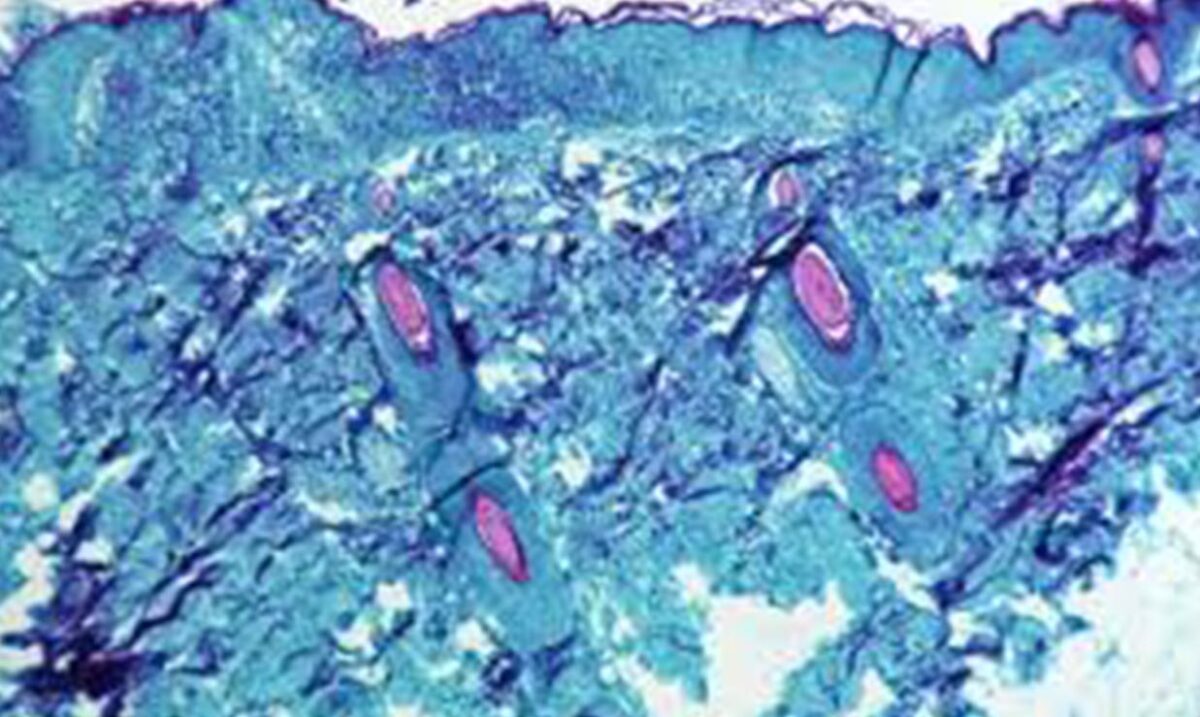

SESA informó a la población que la viruela símica suele ser una enfermedad autolimitada, con síntomas que duran de 2 a 4 semanas. Los signos clínicos suelen ser fiebre, erupción cutánea e inflamación de los ganglios linfáticos.

Es necesario saber, que de acuerdo con la Organización Mundial de la Salud (OMS), el cuadro clínico de la viruela símica se asemeja al de la viruela, la cual es una infección que se declaró erradicada en todo el mundo en 1980. Sin embargo, la viruela símica es menos contagiosa que la viruela y causa una enfermedad menos grave.